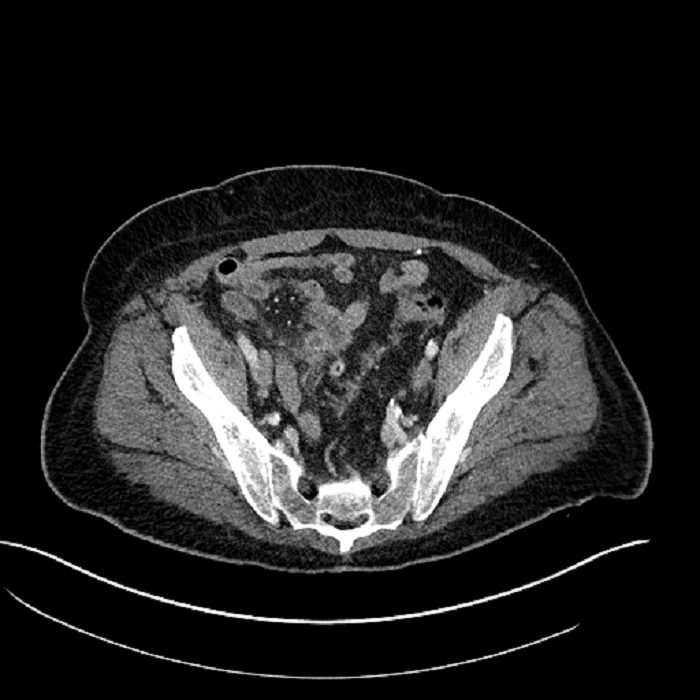

• Mild mural thickening of a segment of the sigmoid colon with adjacent fat stranding and a 1.5 cm fluid and gas collection along the tip of an inflamed diverticulum

• Loss of the normal fat plane between this collection and adjacent loops of small bowel, which demonstrate mural thickening

• No bowel obstruction

• High grade stenosis of the left common iliac artery, with the left internal and external iliac arteries remaining patent

Acute sigmoid diverticulitis complicated by a small contained perforation and a large abscess in the right hepatic lobe. Additional small subcapsular abscesses along the anterior margin of the left hepatic lobe.

Additionally, loss of the normal fat plane between the peridiverticular collection and adjacent thickened loops of small bowel raises the potential for an enterocolonic fistula.

High grade stenosis of the left common iliac artery. The left external and internal iliac arteries are patent.

Hepatic abscess showing the double target sign with low density internally surrounded by a thin inner enhancing rim (red arrow) and ill-defined outer low density rim (yellow arrow). Blue arrow indicates an internal septation. Red arrows: additional smaller subcapsular abscesses. Red arrow: focal contained perforation associated with diverticulitis.